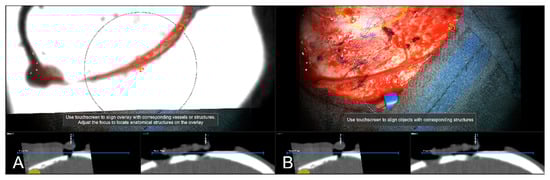

Figure 6.

Navigation inaccuracy seen in the recent focus plane utilizing a MIP of the intraoperative automatic registration CT image set acquired after craniotomy showing the translational mismatch of MIP and patient anatomy (A) and the match of MIP and patients anatomy in the recent focus plane after manual correction (translation) of the visual misalignment (B). (In parallel view of MIP projection (upper part) and inline views with the recent focus plane (blue line) and the optical axis (dashed blue line) in the bottom part).

In 242 cases (82.59%), a vascular representation gained by available preoperative CTA, T1-CE, or ToF angiography data was used to evaluate navigation accuracy after dural incision, whereas in the remaining 18 cases (6.14%), no sufficient representation of cortical vascular structures could be obtained due to a lack of sufficient 3D data or poor contrast enhancement. In 43 out of those 242 cases (17.77%), a need to further realign the image data within the recent focus plane (see Figure 7) was seen, whereas in 181 cases (74.79%), navigation accuracy was determined to be sufficient (see Figure 8), partially due to prior evaluation utilizing bony landmarks. In all 43 cases, showing an inaccurate match of image and patient data, these local inaccuracies were successfully compensated for by rigid 2D transformation of the image data by translation on average of 3.00 ± 1.93 mm and a rotation on average of 0.38° ± 1.06°.

Figure 7.

Navigation inaccuracy visualized in the recent focus plane utilizing a MIP of a preoperative T1-CE image showing the translational mismatch of MIP and patient anatomy (A,B) and the match of MIP and patients anatomy in the recent focus plane after manual correction (translation) of the visual misalignment (C,D). (In parallel view of MIP projection and patient anatomy (upper part) and inline views with the recent focus plane (blue line) and the optical axis (dashed blue line) in the bottom part).